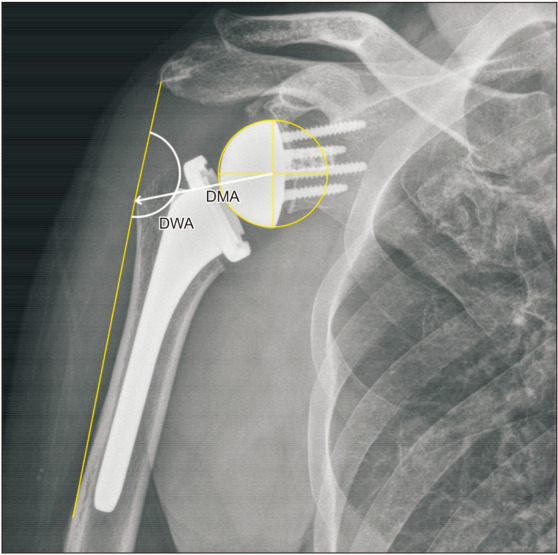

背景:临界肩角(CSA)是一项重要的放射学测量,与三角肌和肩袖生物力学密切相关。我们假设CSA影响逆行全肩关节置换术(RTSA)前后肩关节的生物力学。方法:156例肩胛内侧/肱骨外侧设计行RTSA的患者,根据术前CSA情况分为低CSA组(< 30°)、中CSA组(30°-35°)、高CSA组(> 35°)。通过x线及ct测量三组患者术前、术后肱骨外侧偏移量(LHO)、肩肱距离(AHD)、术后三角肌包裹角(DWA)、三角肌力臂(DMA),并进行比较。比较三组患者在休息和运动时疼痛评分、美国肩关节外科医生评分、加州大学洛杉矶分校肩关节评分和Constant肩关节评分的改善情况。结果:低CSA组术后LHO最大(16.62±4.76 mm),高CSA组术后LHO最小(13.68±5.59 mm, p = 0.03)。术后AHD以低CSA组最高(28.72±5.42 mm),高CSA组最低(25.21±5.12 mm) (p = 0.004)。两组术后DWA、DMA及临床评分改善无显著差异(p < 0.05)。术后发生肩峰骨折5例(3.2%),其中中度CSA组1例,高CSA组4例。结论:低CSA患者肱骨侧化设计的RTSA比中CSA或高CSA患者的肱骨侧化和远端化更多,尽管差异小于5mm。与三角肌活动相关的影像学和术后临床结果的改善,如活动范围、DWA和DMA,在不同csa患者之间没有显著差异。因此,在RTSA期间,CSA对肱骨成分的选择没有帮助,因为基于CSA的临床或功能结果没有显着差异。

Methods: One hundred and fifty-six patients (156 shoulders) who underwent RTSA with medial glenoid/lateral humerus design were divided into 3 groups according to preoperative CSA: low CSA group (< 30°), intermediate CSA group (30°-35°), and high CSA group (> 35°). The preoperative and postoperative lateral humeral offset (LHO) and acromiohumeral distance (AHD) and postoperative deltoid wrapping angle (DWA) and deltoid moment arm (DMA) were measured on x-ray and computed tomography and compared between the 3 groups. The improvement of the pain score, assessed using the visual analog scale at rest and motion, American Shoulder and Elbow Surgeons score, University of California, Los Angeles shoulder score, and Constant shoulder score were compared between the 3 groups.